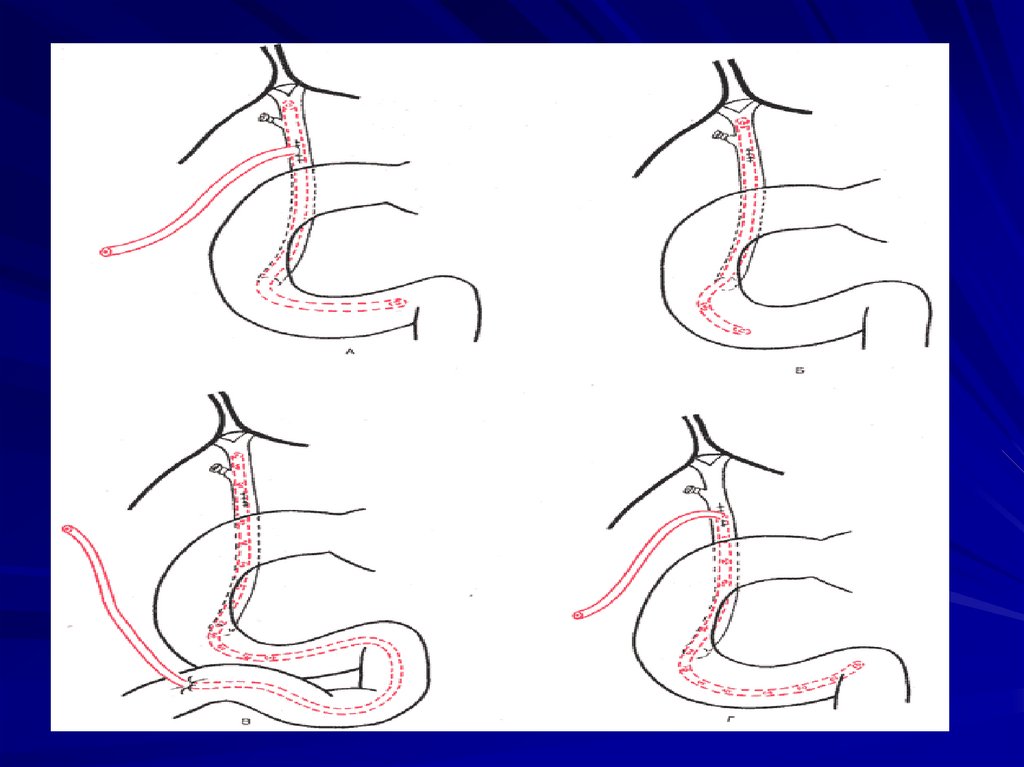

81. ДРЕНИРОВАНИЕ ХОЛЕДОХА

А

Б

В

Г

по Керу

по Кёрте

по Вишневскому

по ХолстедуПиковскому

Д по Аббе

83. Принципы дренирования желчевыводящих путей

А По Робсону

Б По Вишневскому

В По Денверу-Керу

Г По Стерлингу